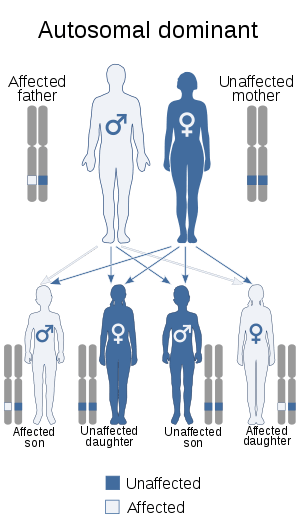

| Noncompaction cardiomyopathy is inherited in an autosomal dominant manner | |

The American Heart Association's 2006 classification of cardiomyopathies considers noncompaction cardiomyopathy a genetic cardiomyopathy.[5] Mutations in LDB3 (also known as "Cypher/ZASP") have been described in patients with the condition.[6] There is recent information in which NCC has been seen in combination with 1q21.1 deletion Syndrome.[7] Furthermore mutations in Titin (TTN), RBM20 and also LMNA could be detected in a large cohort of LVNC patients.[8] In addition, a small in-frame deletion was identified in the DES gene, encoding the intermediate filament protein desmin.[9]